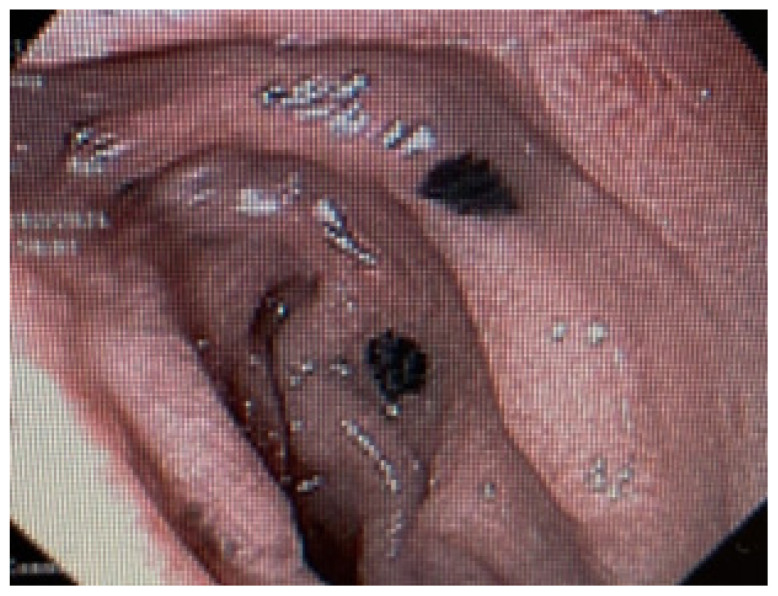

Disseminated Melanoma with Extensive Gastrointestinal Tract Involvement: Incidental Detection of Metastases on Upper Endoscopy.